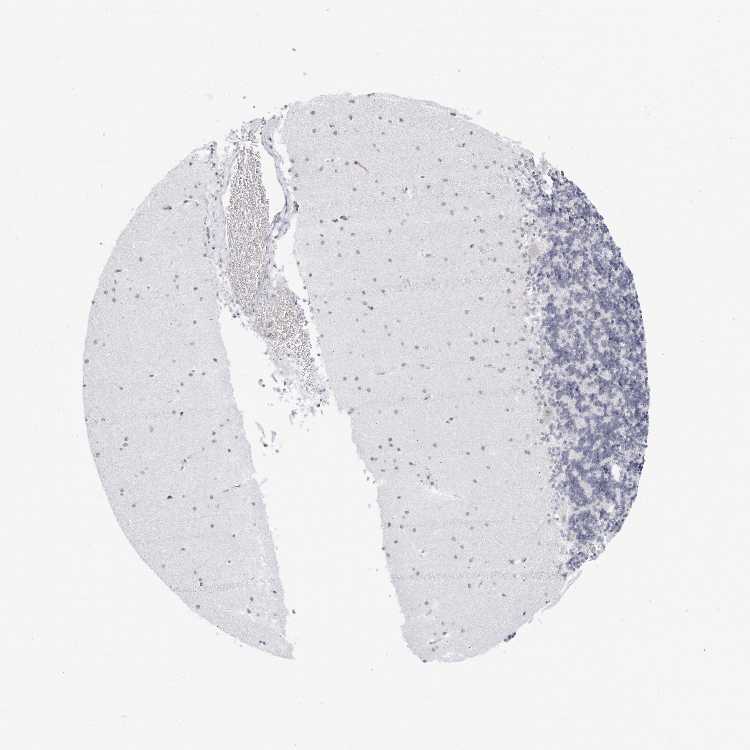

CEREBELLUM - Antibody stainingi

Antibody staining in the annotated cell types in the current human tissue is reported as not detected, low, medium, or high, based on conventional immunohistochemistry profiling in selected tissues. This score is based on the combination of the staining intensity and fraction of stained cells.

Each image is clickable and will lead to virtual microscopy that enables deeper exploration of all samples and also displays staining intensity scores, fraction scores and subcellular localization as well as patient and tissue information for each sample.

Antibody HPA028177Antibody HPA028180Antibody HPA028182

Purkinje cells Not detectedNot detectedNot detected

Cells in granular layer Not detectedNot detectedNot detected

Cells in molecular layer Not detectedNot detectedNot detected